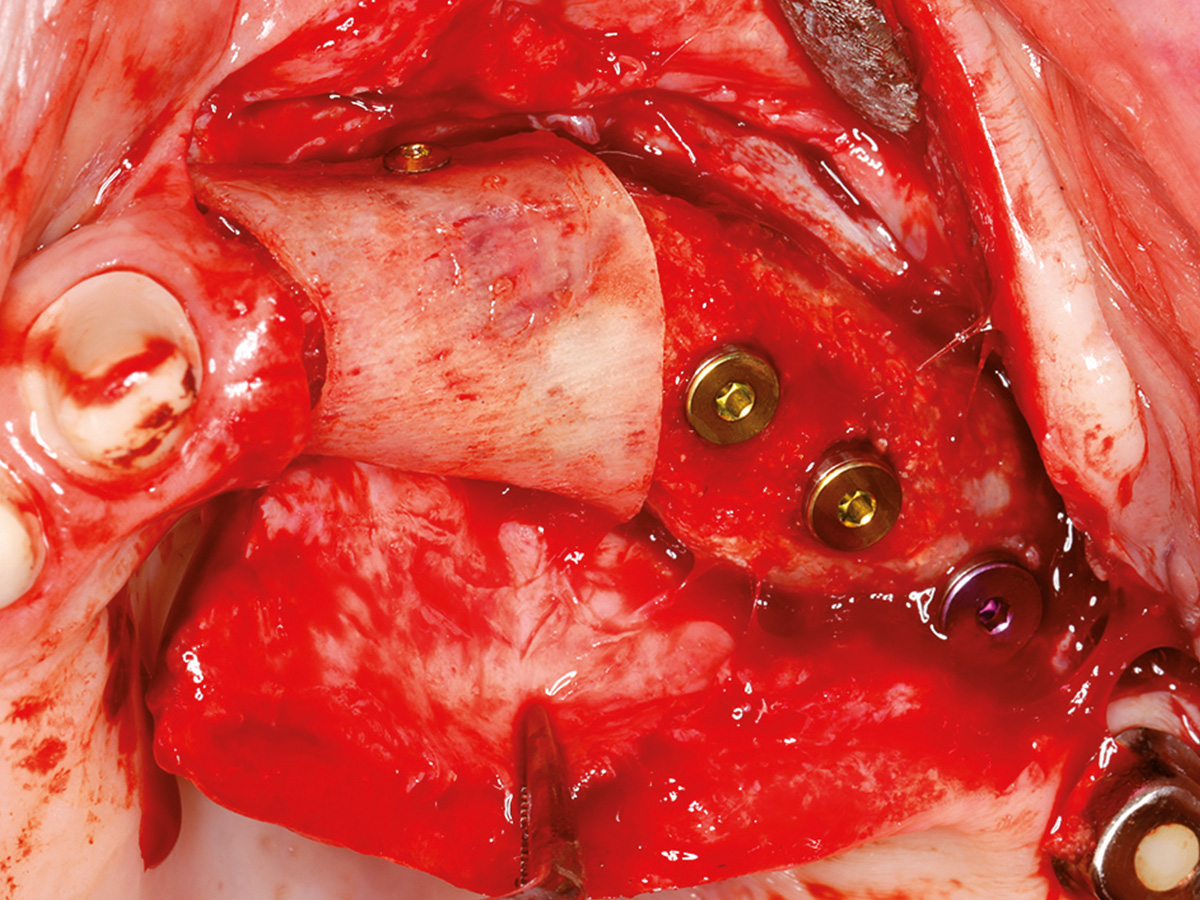

In diesem Kurs wird das Handling mit der Bone Lamina samt Augmentation geübt. Danach sollte jeder Teilnehmer inder Lage sein, im Praxisalltag Knochen aufzubauen. Dazu isteine korrekte Schnittführung notwendig, die ebenfalls thematisiert wird. Damit ein Knochenaufbau erfolgreich einheilt, ist der spannungsfreie Wundverschluss zwingend erforderlich.Deshalb wird im Kurs auch besonderes Augenmerk auf spezielle Nahttechniken gelegt, die am Modell und am Schweinekiefer geübt werden.